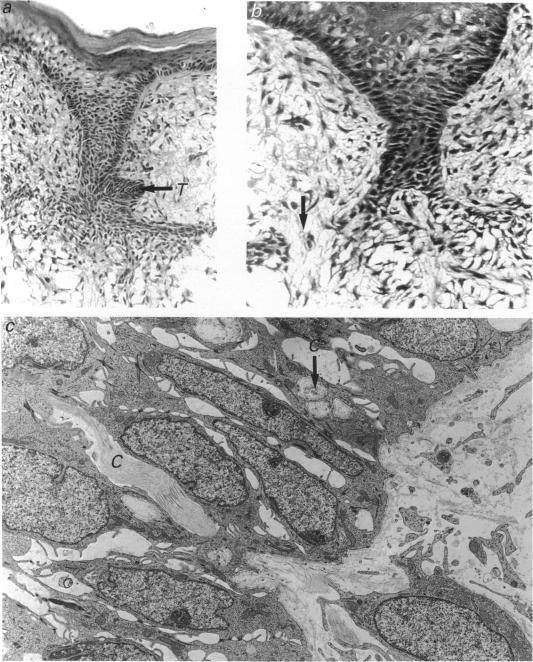

The lamina of the first mandibular molar teeth of rats, age range 13 d intrauterine (i.u.) to 16 d postnatal (p.n.), was examined by light and transmission electron microscopy to establish histological baselines of its development and fate. All material was obtained from animals anaesthetised with ether, killed by cervical dislocation and prepared by routine methods for both types of examination. Contrary to earlier reports that the lamina remains intact throughout development, mesenchymal elements disrupt the lamina. These were seen first at 19 d i.u., as collagen-filled bays in the basal epithelial layers, associated with partial loss of related basal lamina. In the early stages, collagen deposition was limited and it was not obviously preceded by epithelial cell death or transformation, even though many bay-related cells showed lipid and glycogen accumulations. Later disruption of the lamina showed more mesenchymal cells as well as collagen in deeper spaces. After the onset of tooth eruption, mesenchymal cells external to and within the lamina contained lysosomal bodies and these plus evidence of related epithelial cell death and capillaries in the laminar spaces became more and more apparent. Similar collagen deposits were observed in a successional tooth primordium, which appeared at term but eventually aborted between days 5 and 10 p.n. Thus disruption of the lamina by connective tissue began earlier than has been reported previously and progressed as the tooth erupted towards the oral cavity. The evidence suggests that this disruption is initiated and sustained by mesenchymal cell activity rather than by programmed cell death or transformation of the epithelium.

对年龄范围为子宫内13天至出生后16天的大鼠第一下颌磨牙牙板进行了光镜和透射电镜检查,以建立其发育和命运的组织学基线。所有材料均取自用乙醚麻醉、经颈椎脱臼处死的动物,并通过常规方法制备用于两种类型的检查。与早期报道称牙板在整个发育过程中保持完整相反,间充质成分会破坏牙板。这些最早在子宫内19天时可见,表现为基底上皮层中充满胶原的凹陷,伴有相关基底膜的部分缺失。在早期阶段,胶原沉积有限,且在其之前并没有明显的上皮细胞死亡或转化,尽管许多与凹陷相关的细胞显示出脂质和糖原积累。牙板后期的破坏显示在更深的间隙中有更多的间充质细胞以及胶原。在牙齿萌出开始后,牙板外部和内部的间充质细胞含有溶酶体,这些以及层状间隙中相关上皮细胞死亡和毛细血管的证据变得越来越明显。在一个相继牙胚中观察到类似的胶原沉积,该牙胚足月出现,但最终在出生后第5天至第10天之间退化。因此,结缔组织对牙板的破坏比以前报道的要早开始,并随着牙齿向口腔萌出而进展。证据表明,这种破坏是由间充质细胞活性引发和维持的,而不是由上皮细胞的程序性死亡或转化引起的。